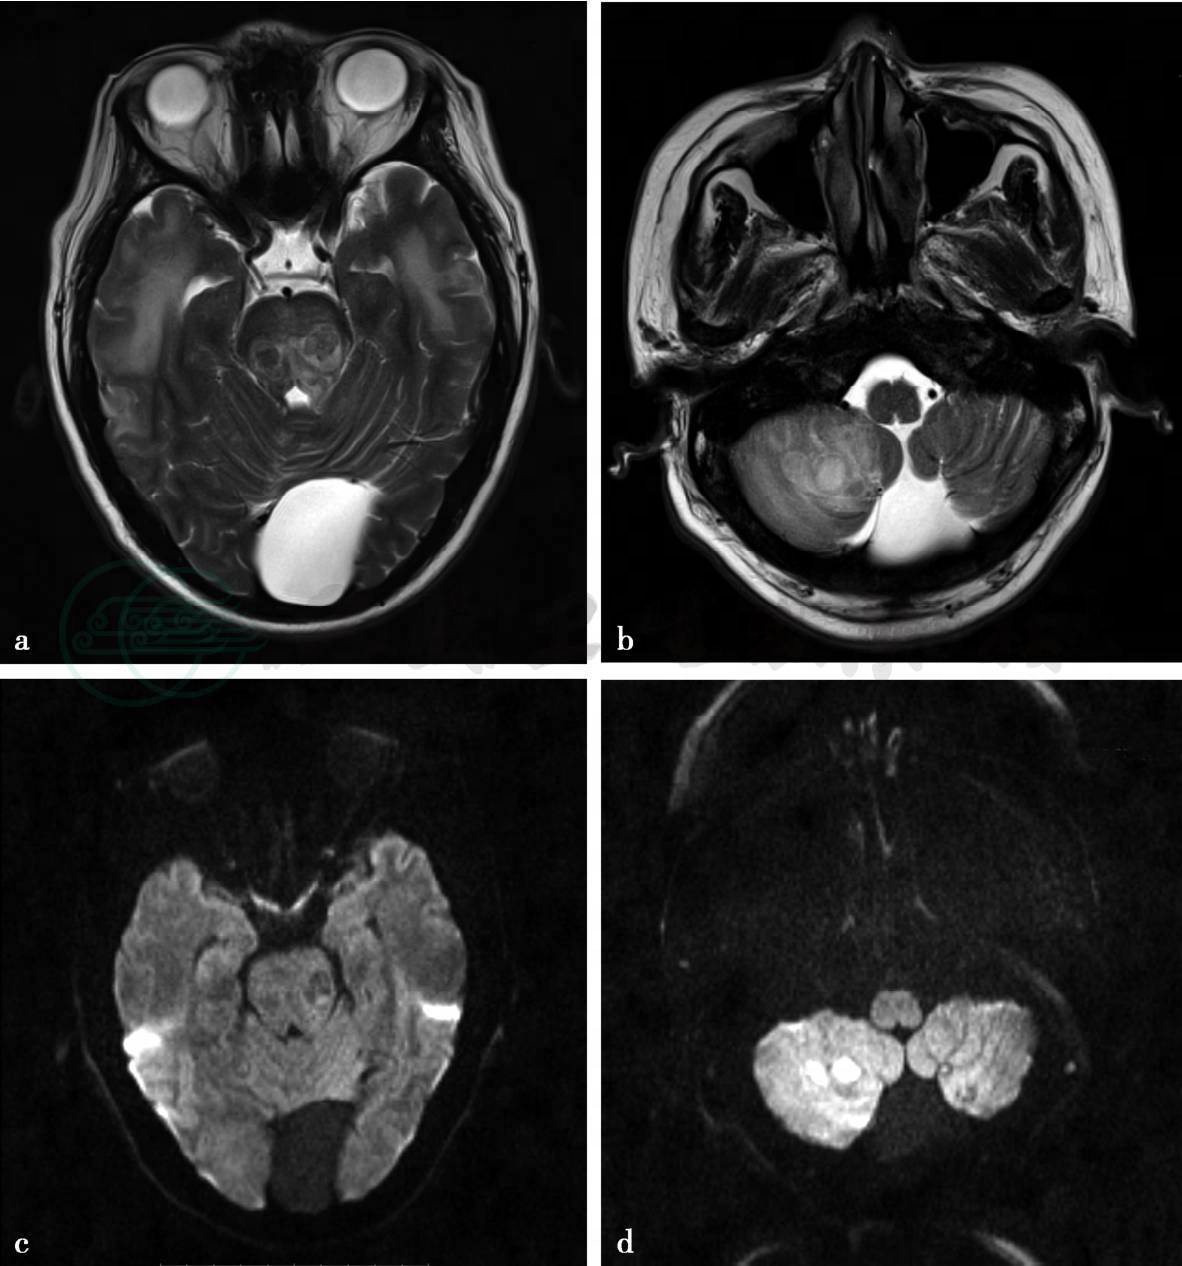

(2)病例7,男性,42岁。发热、乏力2个月余,发作性意识丧失10天。脑脊液:白蛋白434.6mg/L,免疫球蛋白IgG 161.0mg/L。胸部正位片:播散性肺结核。

(2)病例7:

MRI平扫及增强扫描。

图2 a,T2WI见双侧大脑脚呈类圆形等或稍高信号病变,周边伴有水肿。双侧颞叶片状水肿,后颅窝可见蛛网膜囊肿。b,T2WI见右侧小脑半球两枚类圆形高信号病变,灶周可见水肿。c,DWI上双侧大脑脚病变无明显扩散受限,呈略低信号。d,DWI上右侧小脑半球病变扩散受限呈明显高信号。e~f,T1WI增强扫描见双侧大脑脚病变呈环状或多房状强化,双侧颞叶另可见多发小环状强化灶。右侧小脑半球病变呈环状强化,双侧小脑半球可另见多发环状或结节状强化灶

(2)病例7,脑内结核球、结核性脑脓肿。